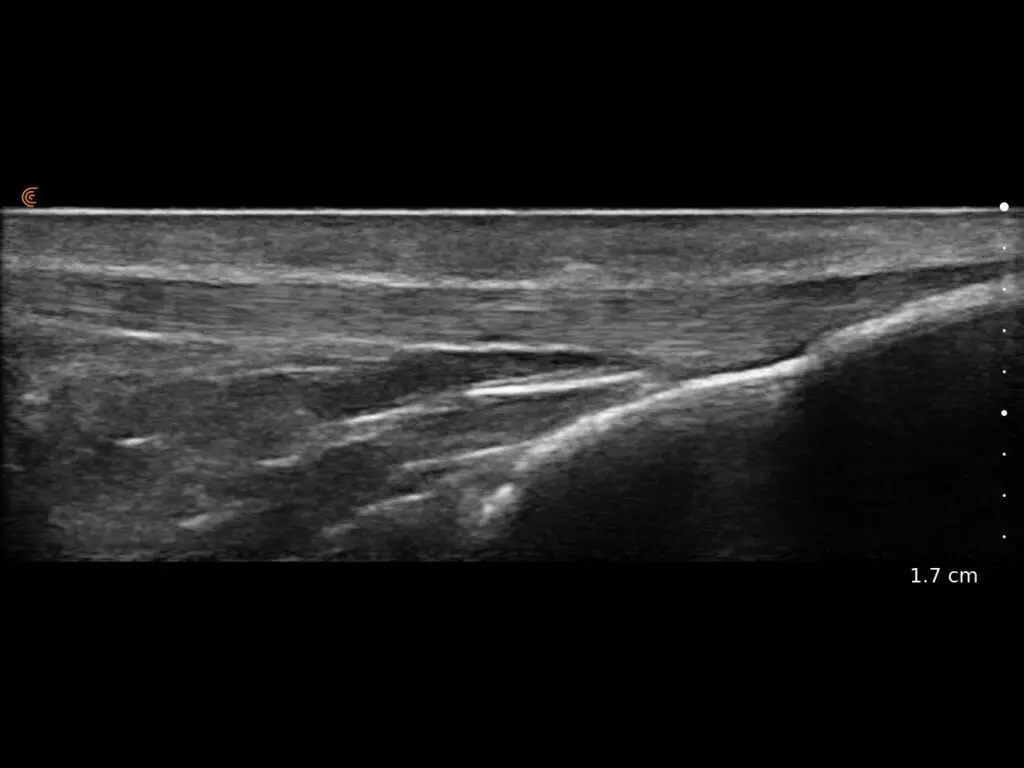

ProbeFix Dynamic is a new device that enables high-quality ultrasound measurements during dynamic exercise by keeping an ultrasound probe in place, allowing for muscle monitoring during intense movement and creating new research possibilities in muscle imaging.